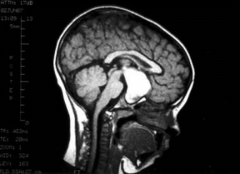

颅咽管瘤 是一种少见的中枢神经系统(CNS)良性肿瘤,被认为是由脑垂体附近的Rathkes囊残余形成。它们占全部原发性中枢神经系统肿瘤的不到1%,但却是儿童...

颅咽管瘤是一种来源于胚胎残余组织的良性肿瘤,颅咽管瘤约占儿童全部脑瘤的6%。任何年龄的人都有可能被诊断为颅咽管瘤,但在5到14岁之间较容易被诊...

如果肿瘤很大,会导致垂体附近的其他神经或动脉受压,是将眼睛与大脑连接的视神经。颅咽管瘤本身不是垂体瘤,而是在垂体腺附近及其上方,在将眼睛...

颅咽管瘤能活多久?颅咽管瘤是在儿童或成年期期间诊断出的少见鞍区肿瘤,多发生在分泌多种激素的垂体附近...